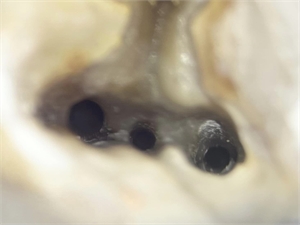

Root canal orifices of a molar tooth - clinical picture taken under microscope

Endodontics is the area of dentistry that cleans and fills the root canals. O the picture you can see the openings of the canals or so called root canal orifices

A root canal orifice is an important landmark in operative dentistry. Root canal treatments are usually done to eliminate all the infective material from the root canals of the tooth. In order to do so, the dentist needs to first deroof the pulp chamber. Once the pulp chamber is removed, the dentist can locate the root canal orifices.

In most cases, the root canal orifices are equidistant from each other. However, this is uncommon in upper back teeth. When the dentist drills the tooth to gain access to the root canal, then the cavity thus made must be enlarged enough for proper visualisation of the floor. The root canal orifices are present at the junction of the walls and the floor of this cavity.

The root canal orifice is the point where the dentist introduces his instruments in order to clean and shape the root canals. In many cases the root canal orifices are too small and it might be difficult to pass an instrument through it. In such cases, an orifice opener bur is used to widen the orifice. The procedure to locate the root canal orifices is similar in deciduous or milk teeth as well. The only difference is that the orifices are located at a relatively higher position due to the decreased length of the tissues and hence are found earlier. On a digital radiograph, a close inspection of the pulpal floor might reveal a few blackish spots, that often correspond to the root canal orifices. This is particularly useful in cases where orifices are not located at the conventional areas.